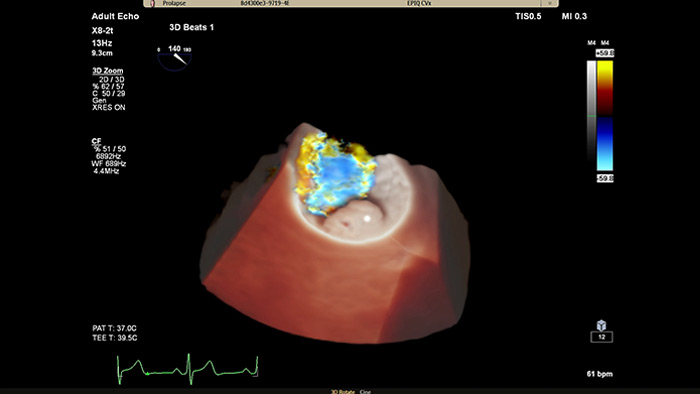

Philips Cardiac TrueVue on EPIQ CVx.

View enhanced visualizations of structures and flow with TrueVue Color